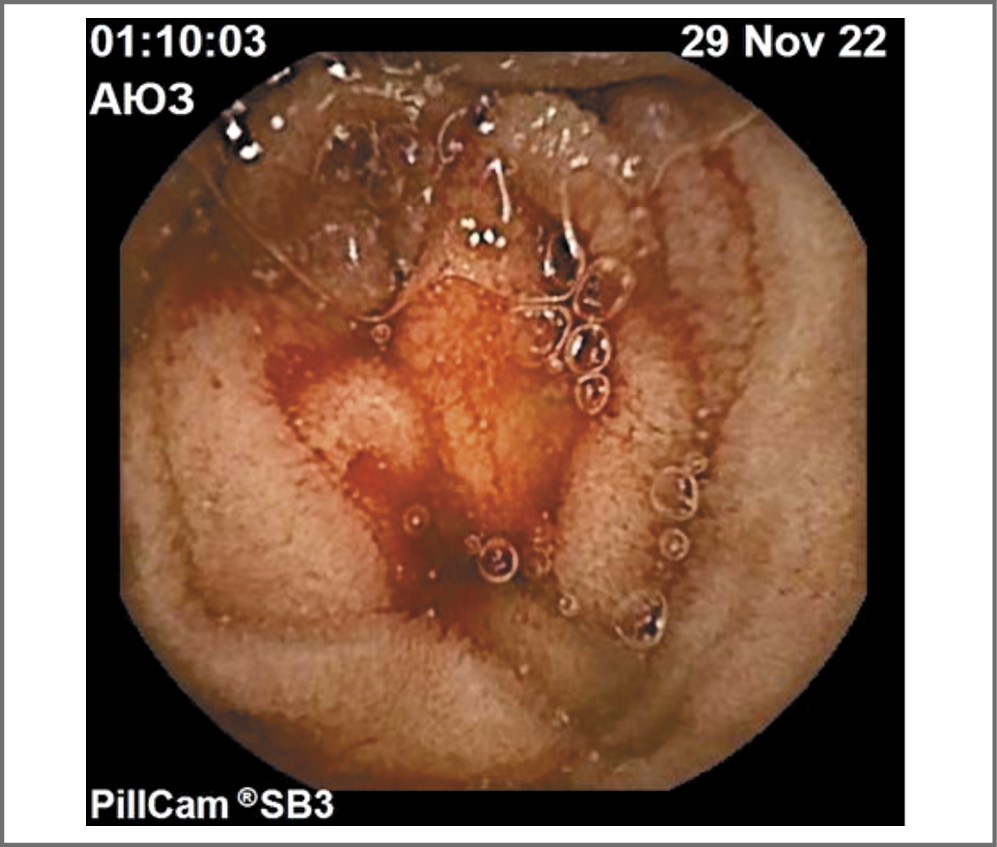

Клинико-инструментальная картина не позволяла исключить наличие источника кровотечения в области тонкой кишки, в связи с чем пациентка направлена в Центр неотложной патологии тонкой кишки на базе ГБУЗ «ГКБ №17», где выполнено дообследование. Больной дополнительно выполнена видеокапсульная энтероскопия, при которой подтверждено наличие множественных телеангиоэктазий слизистой оболочки желудка, двенадцатиперстной кишки, телеангиэктазий тощей, подвздошной, поперечно-ободочной кишки. Кроме того, на момент прохождения капсулы по тонкой кишке зафиксировано продолжающееся низкоинтенсивное кровотечение, наиболее вероятным источником которого являлась ангиоэктазия тощей кишки (рис. 4, 5).

Рис. 4. Телеангиоэктазии тощей, подвздошной кишки у пациентки З.

Рис. 5. Продолжающееся низкоинтенсивное кровотечение тощей кишки у пациентки З.